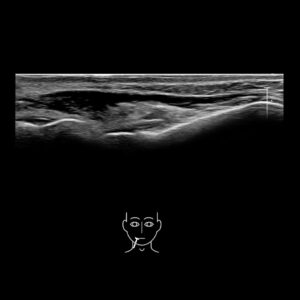

The chin

Study the first image to recognize the different layers. If you are sure about the layers, swipe to the second image to view the answer (if applicable).